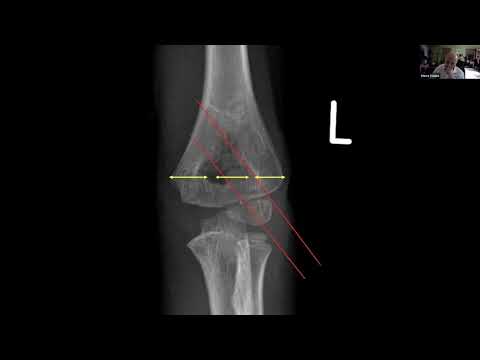

supracondylar fractures: treatment tips and tricks - Stephen Cooke

Fundamentals of Orthopaedics Session 6: Paediatrics Session 1 - Supracondylar Fractures and NAI